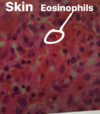

Q

List the tissue type and what cells are circled